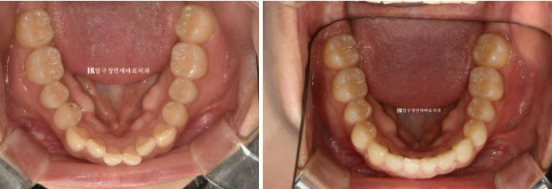

23.10

우측 사진에서 첫번째 작은어금니 교합이 떠 있는 것이 보입니다.

통상 앞니 부분교정은 송곳니에서 송곳니까지 6개 앞니만을 대상으로 하지만, 작은 어금니 교합도 개선하기 위해서

송곳니 뒤쪽 1개씩 총 8개 치아에 장치를 붙이기로 했습니다.

23.10~24.05

교합이 떠 있던 작은어금니도 제자리를 찾았습니다.

앞니가 깊게 물리는 과개교합도 어느정도 해결이 되었습니다.